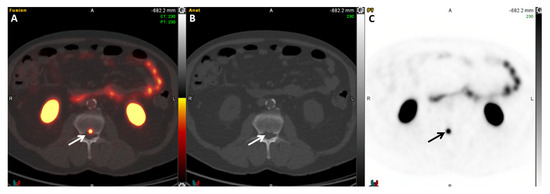

2.3. 18F/11C-Choline PET